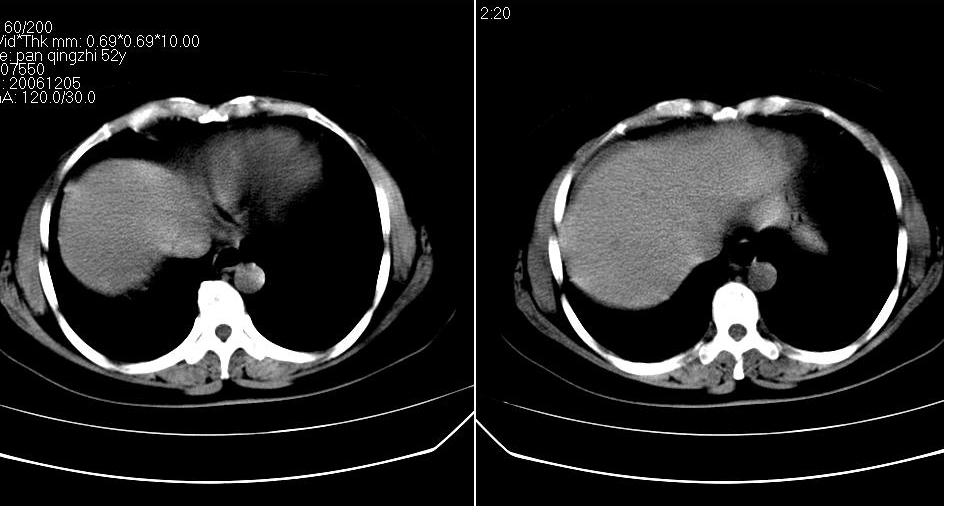

女 52岁,腹痛两天,无其它不适。

慢性胆囊炎,胆囊结石,胆源性胰腺炎考虑假囊肿形成。

胆囊、胆总管结石,胰腺炎,少量腹水。

左肾周筋膜增厚,肾前间隙积液,胰腺肿大,胆囊结石,胰腺炎

胆囊结石 胰腺炎伴胰尾假性囊肿形成.

1、慢性胆囊炎,胆囊结石、胆总管结石。诊断依据:胆囊内、胆总管内见高密度影,胆囊已有萎缩,说明时间已较长,胆囊壁有增厚。

2、胆源性胰腺炎,诊断依据:同1外+左肾周筋膜增厚,肾前间隙积液,胰腺肿大。